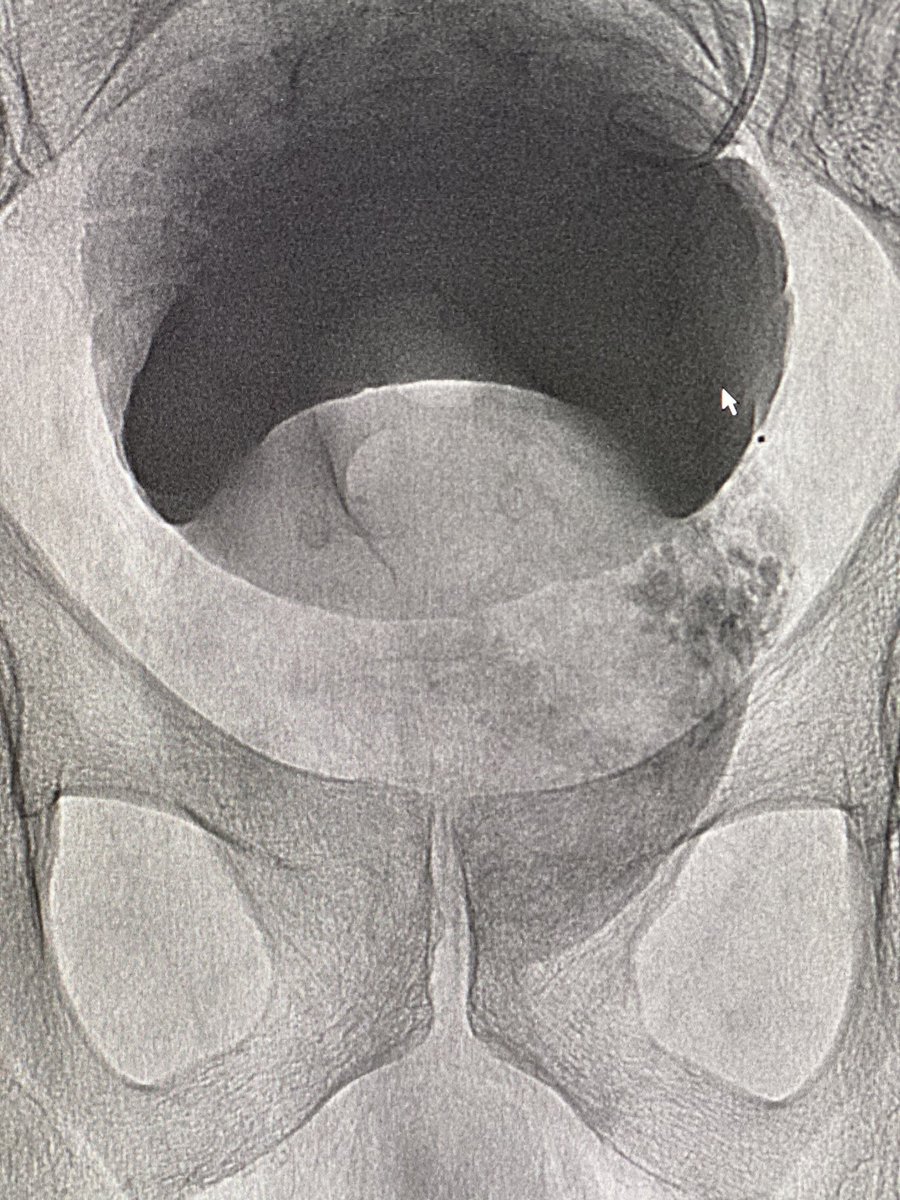

61yr with a whopping 306 cc prostate. #radialfirst #PAE. 1720 mGy. Discharged 90 min post #irad procedure. What’s the biggest prostate would you consider for PAE? @BSIR_News @pairsmedia @cirsesociety @AriIsaacsonMD @TiagoBilhim @BryantTimo